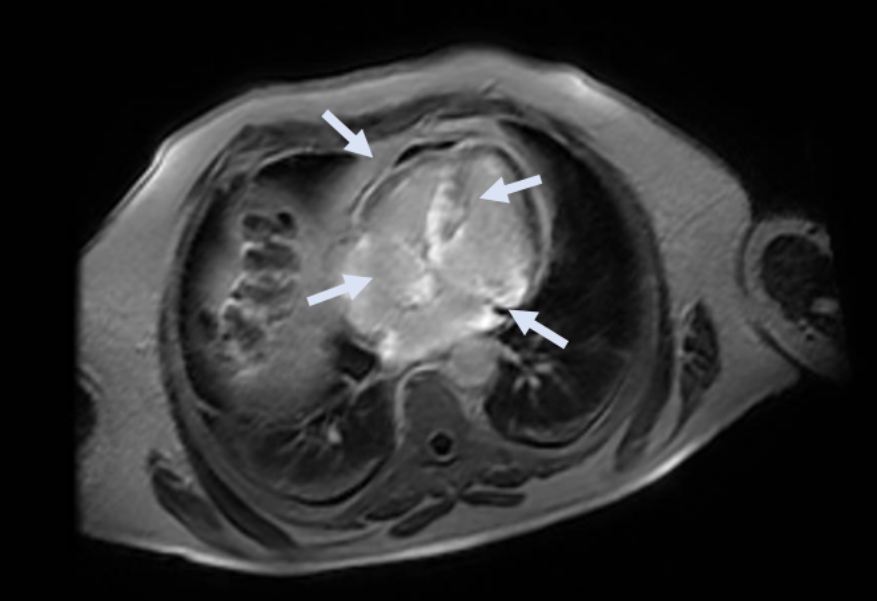

In view of the electro-anatomical discordance and the hypertrophic phenotype detected on the echocardiogram, CMR was performed. These results:

- Biventricular hypertrophy with preserved systolic function

- Infiltrative pattern with extensive areas of late gadolinium enhancement (LGE) predominantly intramyocardial at the level of the basal and middle septum, the basal postero-lateral wall, the papillary muscles and at the subepicardial-intramyocardial site of the anterior mid-basal wall and the inferior wall

- Presence of LGE also at the level of the atrial walls and the thickened interatrial septum

- Also presence of altered gadolinium kinetics, characterized by rapid uptake of the contrast agent into the myocardium at the expense of the blood contained in the cardiac chambers

CMR Images

- CMR: ventricular hypertrophy, altered gadolinium kinetics and diffuse finding of LGE with a non-ischemic pattern also involving the cardiac atria.